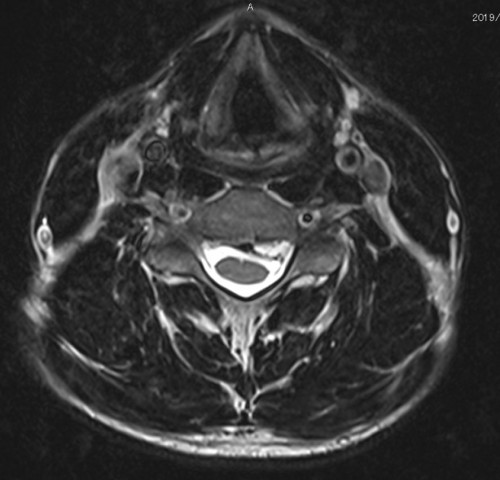

I’ve looked at his MRI scan and it looks like exactly like pictures below: